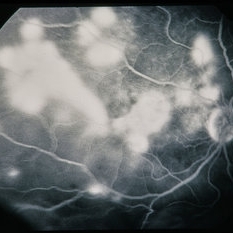

Candida Albicans Endophthalmitis

Mar 17 2013 by David Callanan, MD

28-year-old male with 1 week history of decreased vision. Following biopsy and treatment, patient admitted to illicit intravenous drug use.

Condition/keywords: endogenous endophthalmitis